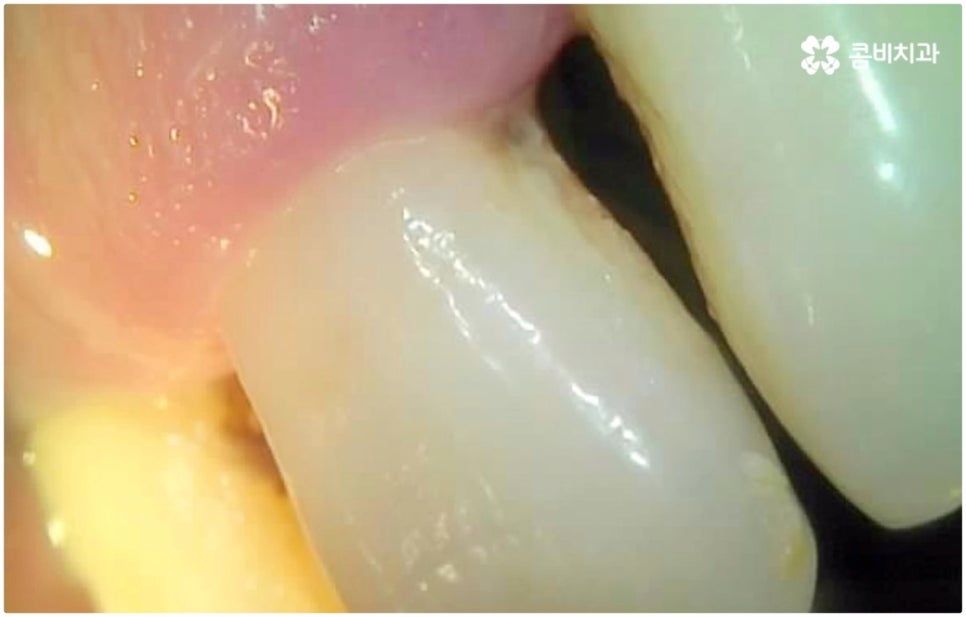

하지만 여기서 주의하셔야 할 점은 누구나 발치후 임플란트 를 즉시 식립할 수 있는 것이 아니라 바탕이 되는 잇몸뼈의 양이 충분하고 기존에 염증과 같은 잇몸 질환이 없는 분들의 경우에만 이용할 수 있는 방법이기 때문에 3D CT 등 정밀 분석 기계로 환자분들의 상태를 정확하게 진단한 후에 결정해야 한다는 거예요.

즉, 해당 분야의 임상 경험이 풍부한 숙련된 의료진분들이 계신 치과에서 자신이 발치후 임플란트 즉시 식립 방식이 가능한지 부터 확인하실 필요가 있는데요. 만약 다양한 이유로 인해 발치 후 즉시 심는 것이 불가능한 케이스라고 한다면 상황에 맞게 뼈이식, 상악동 거상술, 잇몸 질환 치료 등 선처치들을 먼저 해 주고 나서 충분한 회복 기간을 두고 임플란트 시술을 진행해야 식립 성공률 및 지속 가능성을 높일 수 있습니다. 이렇게 환자분들 각각의 상황을 고려하지 않은 채 발치 후 즉시 식립을 무리하게 진행하게 되면 임플란트의 위치를 제대로 고정하는 데 어려움이 있어 해당 치아로 잘 씹을 수 없게 되고 얼마 지나지 않아 다시 쓰러지거나 주변 치아와 잇몸에 압박을 가해서 지속적으로 좋지 않은 영향을 주게 되는 등 문제가 커질 수 있으니 주의하실 필요가 있어요.

임플란트 치아는 사후 관리만 잘 해 준다면 거의 반영구적으로 사용이 가능하기 때문에 이를 위해 임플란트 치아에 갑작스럽게 너무 큰 힘이 가해지지 않도록 조심하고 정기적으로 치과에 내원하여 스케일링 치료 및 검진을 받는 습관을 들인다면 보다 바람직할 거예요. 만약 제대로 관리해 주지 못하면 임플란트가 부러질 수도 있고 임플란트 주위염과 같은 혹시 모를 부작용을 겪을 수도 있는데요. 이는 임플란트 치아 자체의 수명을 짧게 할 뿐 아니라 치조골을 녹이면서 임플란트 치아가 흔들리고 결국 빠지게 만드는 등 더 큰 문제로 이어질 수 있기 때문에 주의하실 필요가 있습니다. 이렇게 잇몸뼈 상황이 안 좋아지게 되면 혹여 재수술을 해야 한다고 했을 때 처음 식립시 보다 훨씬 어려움이 커지게 되고 정도가 심각한 경우 재수술이 아예 불가능 하게 될 수도 있으므로 특히 주변 잇몸 건강에 신경써서 꾸준히 관리해 주시길 권유드리고 있어요.